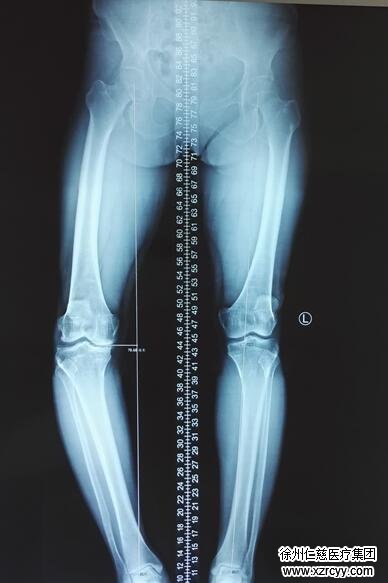

其实乌二枝的腿病在生活中并不少见,这是一种下肢畸形。我们在生活中常常遇到的 “罗圈腿”,也是一种下肢畸形,叫0型腿,医学上称为“膝内翻”,以两下肢自然伸直或站立时,两足内踝能相碰而两膝不能靠拢为主要表现的畸形疾病。单下肢腿内翻者即为D型腿。

“她平时干农活嘛,长期一个姿势,刚开始只是膝盖有点疼,后来情况越来越严重,没有什么好转,听人介绍就来我们这看了。”参与手术的住院医师张恒军拿着片子介绍,“董主任主刀,我们应用伊利扎洛夫技术给她做的矫正。你看,她的小腿部位的骨头明显歪了,手术就是把歪的这个部位截断,把右小腿给她慢慢地掰正。”